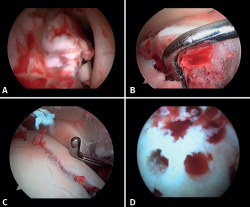

If possible, we reinsert unstable osteochondral fragments (Figure 3). In chondral lesions where it is not possible to reinsert the fragment, cartilage repair stimulation techniques can be used(5,13).

Figure 3. A: loose bodies; B: osteochondral lesion; C: reduction of the osteochondral lesion; D: medullary stimulation.